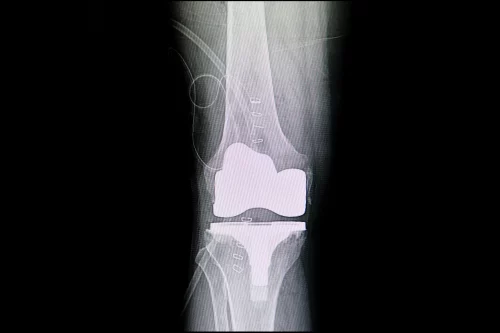

Prótesis de Rodilla

La decisión de someterse a una prótesis de rodilla es significativa. Utilizo técnicas avanzadas y materiales de alta calidad para asegurar que cada paciente reciba una prótesis que se adapte a sus necesidades específicas. Mi experiencia en la implantación de prótesis de rodilla individualizadas impresas en 3D me permite ofrecer soluciones personalizadas y duraderas.

Soy uno de los primeros médicos en Alemania y el pionero en España en la implantación de prótesis de rodilla individualizadas mediante tecnología de impresión 3D. Esta innovadora técnica permite diseñar prótesis que se adaptan perfectamente a la anatomía de cada paciente, ofreciendo un ajuste preciso y una recuperación más rápida. Es un honor ser el referente en España en esta especialidad.